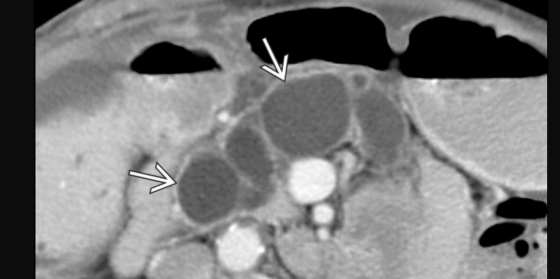

TIPMP mixtes

- Les deux tyes en même temps

TIPMP des petits canaux + wirsung a 6mm